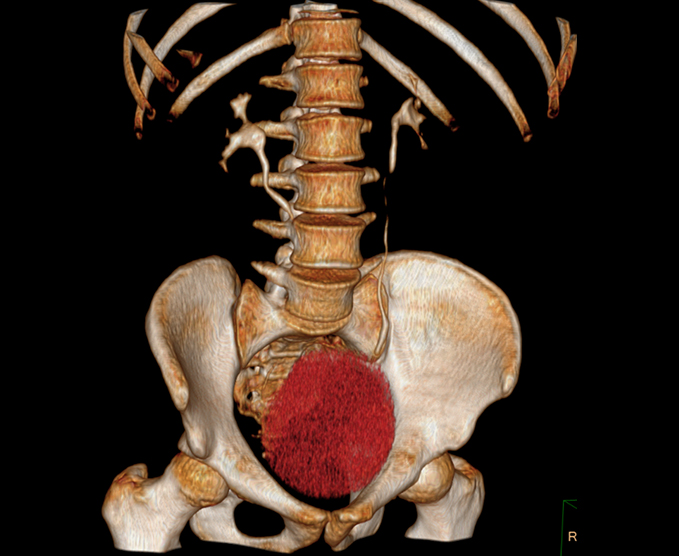

- Abdomen superior e inferior

- Aorta toráccica y abdominal